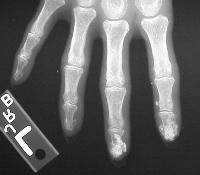

Clinical Example: CREST syndrome with scleroderma, telangiectasias and subcutaneous calcification

Scleroderma is a systemic disease, but commonly affects the hands in several ways. Finger stiffness is typical. Scleroderma may be associated with other syndromes, and a common combination is Calcinosis, Raynaud's, Esophageal motility disorders, Scleroderma and Telangiectasias - CREST syndrome. In this syndrome, the hands are affected by calcinosis, Raynaud's and scleroderma. Skin ulcerations may arise from Raynaud's related peripheral vascular insufficiency (fingertips), from scleroderma related skin tightness (extensor surfaces of the proximal interphalangeal or metacarpophalangeal joints), or from extrusion of subcutaneous calcium formations (any location).

Xrays show extensive soft tissue calcifications of the distal pulp of these fingers.